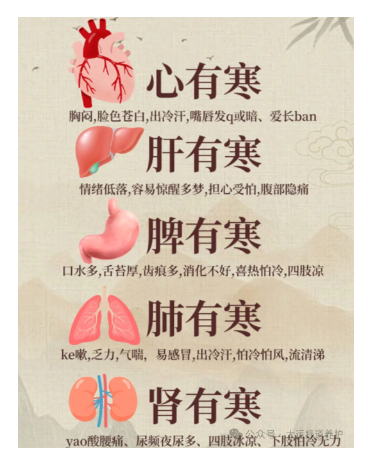

人体气血的圆运动是一个环环相扣的紧密系统,任何一脏的气都和他脏直接相关,如果一个环节出现寒凝淤堵,都会引起蝴蝶效应般的连锁反应,寒气如果长期在身体里周流,可见危害有多大。很多人并不知道自己到底是寒还是热,很多时候觉得自己寒,又有些时候觉得自己热,寒热的体验我们每个人都会有,五脏都有寒热之分。今天我们就一起来了解一下这方面的内容,看看心寒、肺寒、脾寒,肝寒、肾寒,各有什么表现,自己或身边的人出现症状时,可以明确知道自己更适合做哪方面的脏腑调理。心是君主之官,心寒了,身体就萎靡不振,做什么事都没有兴趣了。我们身体的阳气有两个来源,一个就是心阳,一个就是肾阳。心阳就好比太阳,心寒了就好比太阳失去了光芒,天空一片阴霾,大地一片死寂,万物将会凋零。如果心寒,面色就会苍白如雪,因为心,其华在面。嘴唇发青发紫,身上容易长很多斑,脸上、舌头上、手上、腿上都会长斑,因为心主血脉,各种斑斑点点就是血脉不通的表现。身上各种莫名其妙的淤青,稍微磕着碰着一大块淤青。心脏跳动缓慢,易导致大气下陷,时常叹气,总觉得胸闷、气短,总想深呼吸一口气,遇冷则心痛发作。心寒了,还会出冷汗,因为汗为心之液,心阳不足就无法固摄汗液,汗就容易出来。心寒的人,无欲无求,无所事事,碌碌无为,做什么都觉得没有意思,也几乎没有什么欲望了,有时候,甚至连食欲也没了。所以抑郁症的人一定要从心上调理,强 壮他们的心阳,驱除他们心中的刺骨寒意。肺是相傅之官,肺朝百脉,肺就像宰相,是一人之下万人之上,肺寒了,这座连接心与百脉的桥梁就会垮掉,肺寒了,全身经络就会堵塞。肺寒就会流清鼻涕,稍微着点凉,鼻涕像清水一样流下来。特别容易风寒感冒,因为卫气不足。没有阳气化开肺中的水液,就会凝结成痰,这样的痰颜色是白的,会不停地吐痰。容易不停地咳喘,这种咳喘夜间严重,有很多白痰,秋冬容易发作。肺寒者必气虚,身体总觉得没劲,没力气干活,老想躺着,因为肺主一身之气。肺寒的人不太容易出汗,因为肺主皮毛,肺的宣发能力不够出汗就很少,即使是夏天也很少出汗。肺寒者,还可能会便秘,是那种大便不硬,排便吃力,大便比较细的便秘。肺寒之人一定不要喝冷饮,形寒饮冷则伤肺。脾得温则运化,脾寒了就运化不起来,脾胃是五脏六腑的中心,脾胃不运化整个身体都会出问题。很多人都有胃强脾弱的毛病,吃啥都拉肚子,完谷不化,其中一个重要的原因就是脾寒了。脾喜欢温,不喜欢寒凉。如果脾寒了,就会有很多湿气,因为脾为湿气之源,脾寒不运化,湿邪就会停留身体,泛滥成灾。所以祛湿一定要温脾、健脾。脾寒了,面色就会萎黄,吃东西会积食,就算吃的不多也运化不了,堆在身体就会积食,就会发胖。脾寒,要么很多口水,总是吐不完,睡觉口水流下来,要么就是口干,但是喝水又不解渴。经常会腹泻,吃点生冷寒凉就要拉肚子。会容易感到腹胀,下午表现尤为明显,因为下午的阳气渐渐衰弱。脾主肌肉,脾寒的人常年四肢无力,严重的人还会得重症肌无力。肝是将军之官。肝体阴而用阳,阳气是很足的,所以我们常常说肝火大,很少说肝受寒了。肝一般是不受寒的,一旦受寒,就比较严重。肝寒,可能会腹痛,这种腹痛不是肠道的问题,其实就是肝经经过的地方堵住了,是一种隐隐作痛。比较容易出现关节冷痛,其实并不是骨头出了问题,而是维系关节间的筋出了问题。如果说心阳就像天上的太阳,那么肾阳就是潜藏在地壳深处的热能。

肾藏精,这个精化成两股力量,一股叫肾阴,一股叫肾阳。肾寒,首先表现在全身怕冷,不仅仅是手脚冰凉,冬天很难过,夏天很舒服,平常穿衣服比一般人要多很多。会经常腰痛,是那种冷痛的感觉,腰部特别怕冷风吹,用热水袋捂一下舒服很多,因为腰为肾之府。肾寒者会尿频,这种尿频不是那种每次尿很少每次一点点很快又有尿意的那种,而是尿很多,清晰如水,尤其夜尿多。因为肾司二便。同理,还会五更泻,就是早上五点左右起来腹泻。肾寒者比较容易水肿,尤其是腰以下水肿,因为膀胱里面的水液需要肾阳的气化才能被利用或者排泄。很多慢性肾炎的人都是脾肾阳虚。五脏有寒气,可以靠中医艾灸,进行脏腑调理,驱赶寒气。万病从寒起,守护一身正气,寒邪勿犯,才能靠近养生的最终目的“形与神倶”。